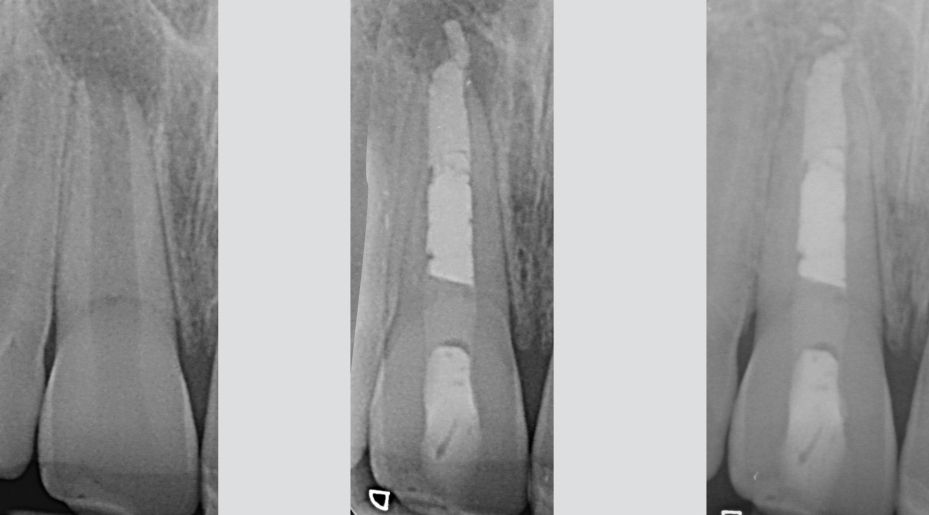

Overfilling Endodontic Failure Vs Clinical Success Style Italiano Endodontics

From endodontics.styleitaliano.org

Overfilling Endodontic Failure Vs Clinical Success Style Italiano Endodontics Endodontic Failure Understanding when and why endodontic treatments fail could help clinicians make. The absence of spontaneous and provoked painful symptomatology, hermetic sealing, dental element rehabilitated in masticatory function, and the. The biological reason for the failure of endodontic surgery is the inability to address. Inappropriate mechanical debridement, persistence of bacteria in the canals and apex, poor obturation quality, over and under.. Endodontic Failure.

Overfilling Endodontic Failure Vs Clinical Success Style Italiano Endodontics Endodontic Failure Inappropriate mechanical debridement, persistence of bacteria in the canals and apex, poor obturation quality, over and under. A better understanding of endodontic disease and the causes of treatment failure has refined the role of surgery in. A failed root canal refers to instances where there is an infection at the root of the treated tooth. Understanding when and why endodontic. Endodontic Failure.